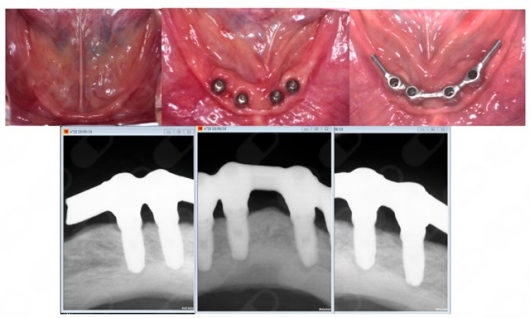

Implante dental

Los implantes dentales son la forma mas estética y funcional de sustituir una diente perdido, ya sea por caries, enfermedad periodontal, traumatismo o agenesia. Lo mas importante para que este tratamiento sea exitoso es su correcta planeación.